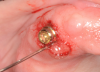

The contours of the prosthesis can have a significant impact on the patient’s ability to maintain good oral hygiene at home and keeping healthy peri-implant tissues. The practitioner should be aware of this issue and make sure restorations are as cleansable as possible. For example, a concave surface from the abutment to the buccal surface is a plaque trap and should be immediately corrected (Figure 5 and Figure 6).

Concavity in the buccal surface of the prosthesis design. The resultant imperfect fit creates a “trap” for plaque.

Figure 5

Figure 6